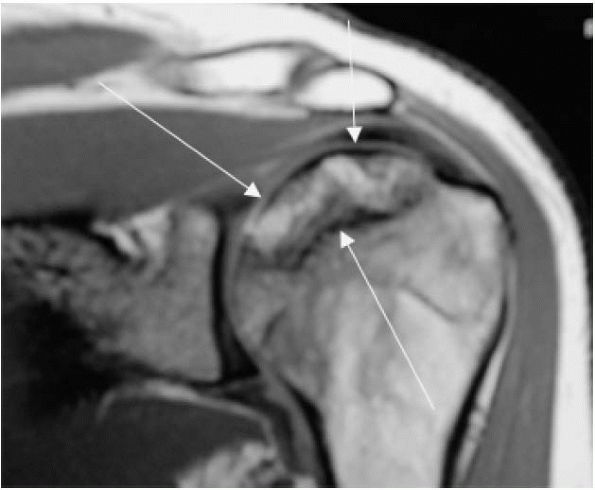

Signal intensity on MRI depends on water and fat variations and

therefore can reveal osteonecrosis prior to radiograph changes (Figure 12-12).

FIGURE 12-12. Coronal MRI image of avascular necrosis of the humeral head (depicted by white arrows).